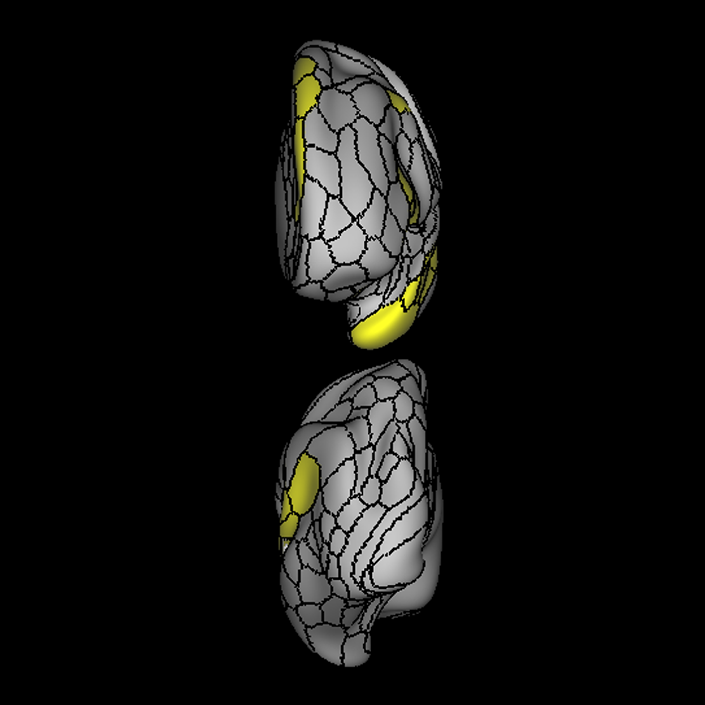

ᐅ SummaryArea 44: part of the inferior frontal gyrus of the lateral frontal lobe. Translates abstract and intentional information in the prefrontal cortex to more detailed representations to help guide the production of verbal and manual actions. In addition to its known association with Broca's area, is sometimes represented as part of Broca's complex ᐅ Where is it?Area 44 is at the posterior most part of the inferior frontal gyrus. It is the anterior bank of pars opercularis of the IFG. ᐅ What are its borders?Area 44 borders area 45 anteriorly and area 6r posteriorly. Area 8C is its medial border and its inferior border is wedged between then upper borders of Areas 6R and 6V. Its superior edge borders IFSp and IFJa. Its opercular surface is FOP4. ᐅ What are its functional connections?Area 44 demonstrates functional connectivity to areas SFL, IFSp, IFJa, 45, 47s, 47L, 9a, 9m, 8AV, 8BL and 8C in the dorsolateral frontal lobe, area 8BM in the medial frontal lobe, area 55b in the premotor areas, areas FOP5, AVI and PSL in the insula- opercular region, areas TGd, STSdp and STSvp in the temporal lobe, areas PFm, and PGi in the inferior parietal lobe, and no areas in the medial parietal lobe. ᐅ What are its white matter connections?Area 44 is structurally connected to the arcuate/SLF and the FAT. Connections with the arcuate/SLF project posteriorly and wrap around the Sylvian fissure to the middle temporal gyrus to end at TE1a and TE1m. There are also projections from the arcuate/SLF before it terminates to parcellations A5 and STSdp. The majority of the inferior connections of the frontal aslant tract end at 44, the tract is connected superiorly to superior frontal gyrus parcellations SFL, 6ma and s6-8. Local short association bundles are connected with 45 and 8C. White matter tracts from 44 in the right hemisphere have less consistent connections with the arcuate/SLF. ᐅ What is known about its function?Area 44 translates abstract and intentional information in the prefrontal cortex to more detailed representations to help guide the production of verbal and manual actions. Area 44, in addition to its known association with Broca's area, is sometimes represented as part of "Broca's complex", including Brodmann Areas 45, 46, 47 and the mesial supplementary motor area of 6, which contribute to a frontal-subcortical circuit. The right pars opercularis has also been implicated in cognitive inhibition in the overall context of working memory. |

A: lateral-medial

B: anterior-posterior

C: superior-inferior

DTI image |